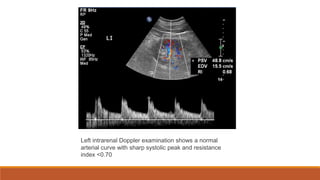

Left intrarenal Doppler examination shows a normal

arterial curve with sharp systolic peak and resistance

index <0.70